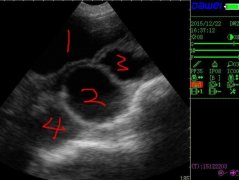

母豬b超_如何給母豬做b超

母豬b超機怎么看出母豬是否懷孕_母豬b超機